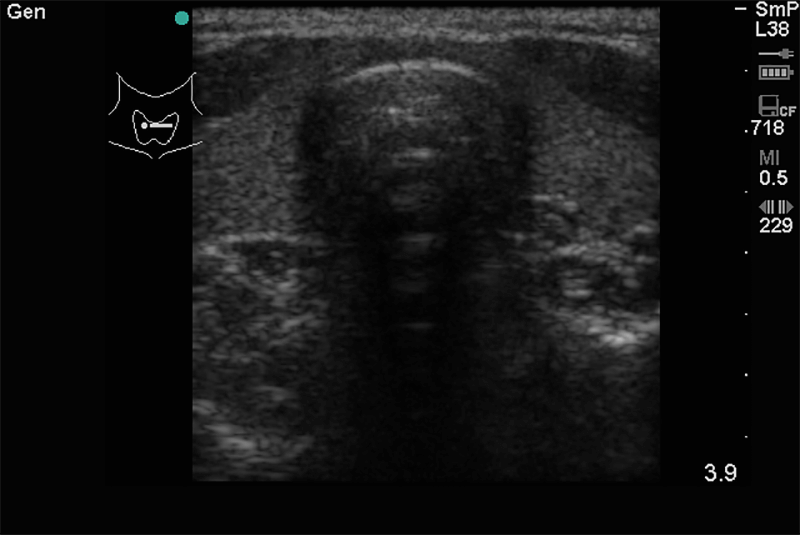

Alapvetően a pajzsmirigy, nyálmirigyek állapotának tisztázása mellett felvilágosítást ad a nyaki nagyerek állapotáról. Kimutathatóak a kóros nyirokcsomók, nyelvgyök körüli, szájfenék alatti, garatkörüli kóros elváltozások.

A nyaki régióban megjelenő kóros duzzanat, csomó fájdalommal vagy anélkül, szorító érzés a torok tájékán, rekedtség és esetleg nyelési zavar utalhat az itt található szervek kóros folyamataira.